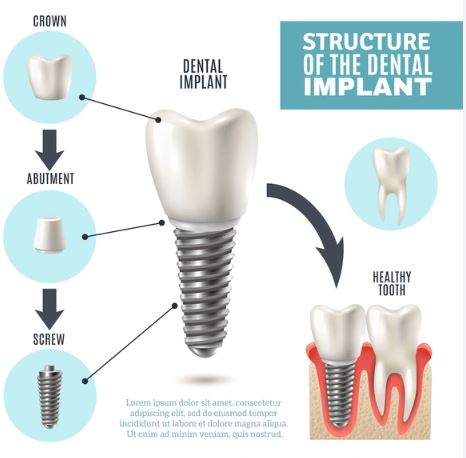

An implant acts as the natural root, supporting a crown, bridge or even dentures. Dental implants do more than restore your smile. They are an investment in your health, preventing bone loss, shifting of teeth, preventing gum disease, and much more.

An Implant is basically a Titanium screw which is anchored to your jaw bone very conveniently & works like your natural tooth.